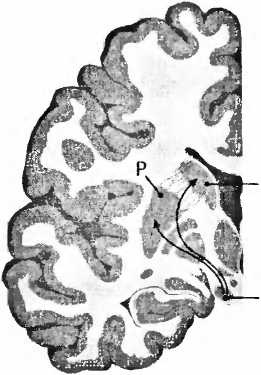

Если трансплантация зародышевой мозговой ткани прошла успешно, какие свойства могут быть приобретены от донора? Для болезни Паркинсона характерно отмирание дофаминовых клеток в черной субстанции (substantia nigra) мозгового ствола (рис. 23). При вскрытии эта область мозга из-за пигментации клеток, вырабатывающих дофамин, выглядит как проходящая через мозговую ткань черная лента. И если эти клетки мертвы, их сразу же видно, как, например, при болезни Паркинсона. Тогда клетки не могут больше иннервировать полосатое тело (стриатум), моторную область в центре мозга, то есть снабжать ее нервными волокнами и управлять ею. Из-за недостатка в стриатуме дофамина возникают типичные для этой болезни расстройства движения. Что может быть логичнее, чем лечить эту болезнь заменой умерших клеток? В1987 году в ведущем профессиональном журнале The New England Journal of Medicine [89] появилась статья мексиканского врача Мадрасо, в которой он сообщал о поразительном улучшении у больного паркинсонизмом после аутотрансплантации ткани дофаминсодержащих клеток надпочечников в хвостатое ядро (nucleus caudatus, рис. 23). В ближайшие два года сообщение привело к лавине из 200 подобных трансплантаций. Но операция оказалась неэффективной, и в течение двух лет после нее 20 % пациентов умерли. Исследование мозга умерших показало, что трансплантированная из надпочечников ткань в мозге не прижилась. В стриатуме были видны только шрамы. Многообещающие результаты Мадрасо были основаны, вероятно, на непрофессионально проведенных исследованиях в сочетании с эффектом плацебо (см. XVII.4). С 1988 года больным паркинсонизмом вместо аутотрансплантации в стриатум ткани надпочечников производят пересадку дофаминсодержащих клеток фетального мозга. Для достижения эффекта ткань должна быть взята у плода возрастом от 6 до 8 недель. Позитронно-эмиссионная томография показала, что при жизни наличие трансплантата можно было установить в мозге примерно 85 % прооперированных пациентов. В стриатуме мозга скончавшегося пациента дофаминсодержащие клетки, связанные с клетками мозга реципиента, были найдены через 16 лет после операции. Но иногда всё же новые дофаминовые клетки также перенимают симптомы болезни Паркинсона. Тот факт, что болезнь иногда переходит на трансплантат, является, возможно, причиной последующего ухудшения состояния пациентов, которые сначала выиграли от операции. Для имплантации необходим материал от четырех эмбрионов. Получить такой материал нелегко, поскольку источником его служит аборт, причем должно быть получено предварительное согласие женщины на трансплантацию. Поэтому сейчас возлагают большие надежды на эмбриональные стволовые клетки как альтернативный источник для трансплантации, так как при их выращивании можно дифференцировать дофаминовые нейроны. В настоящее время, впрочем, эта терапия обладает многими недостатками и таит в себе немало опасностей. Зафиксирован случай, когда у больного через 4 года после инъекции стволовых клеток в мозжечок образовалась опухоль мозга. Из стволовых клеток в принципе может вырасти что угодно, в том числе и опухоль. ![]() ![]() NCSN норма ![]() болезнь Паркинсона Рис. 23. При болезни Паркинсона пигментированные черным клетки, производящие дофамин в черной субстанции (SN), умирают и уже больше не могут управлять моторной областью — полосатым телом стриатумом (Р — putamen, скорлупа; NC — nucleus caudatus, хвостатое ядро). Трансплантация зародышевых дофаминовых клеток в мозг больных паркинсонизмом может иметь определенный успех, так как тогда их лекарство, леводопа, требуется им в меньшем количестве, и к тому же двигательные расстройства снижаются. 11о об окончательном выздоровлении речь не идет, и результаты варьируются. Кроме того, и позитивное воздействие, и побочные эффекты трансплантации те же, что и у леводопы. Примерно в 15 % случаев осложнения при трансплантации проявляются в виде нарушений движений (дискинезии), что возникает также и при приеме леводопы. Проводились плацебо-контролируемые исследования, когда половина пациентов (которые не знали, к какой именно группе они относятся), хотя и были оперированы, не получили трансплантата. Через два года, в том, что касается двигательных расстройств, не было никакой разницы между мнимо оперированными пациентами и пациентами с трансплантатом. В итоге убедительных результатов до сих пор не имеется (см. XVII.4). |